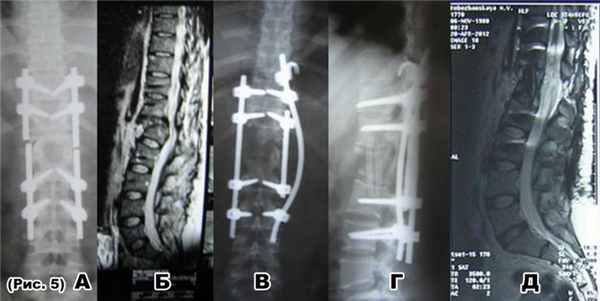

Декомпрессивно-стабилизирущие операции при неудачных операциях на позвоночнике

а) перелом стержней транспедикулярного фиксатора после неудачной операции на позвоночнике по поводу ПСМТ: переломовывихTh12 и компрессионно-оскольчатого переломаL1 позвонка;

б) на МРТотсутствует костный блок между Th11 и L1 позвонком, сохраняется стеноз позвоночного канала

в) и г)декомпрессивно-стабилизирующая операция: спондилодез аутотрансплантатами из ребраTh11-L2, гибридная фиксацияTh9-Th10-Th11-L2-L3 позвонков

д) на МРТ через 1-год после операции сформирован костный блок между Th11- L1 позвонками, стеноза позвоночного канала не определяется.